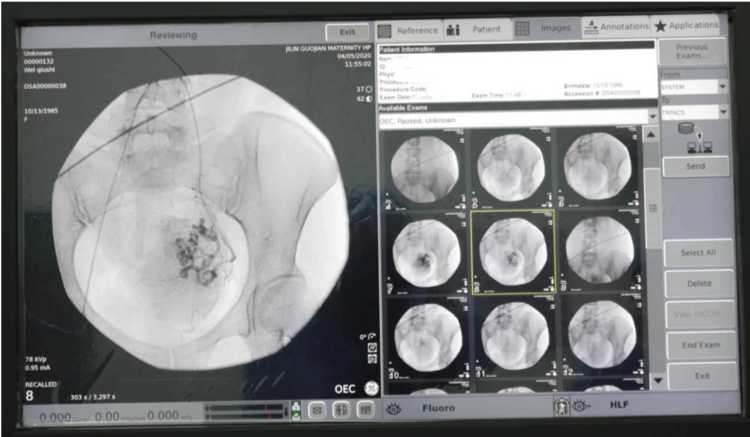

介入治疗的的诊疗范围可以说是非常广泛,具体到妇产科上主要有:子宫肌瘤、子宫腺肌症、异位妊娠、输卵管性不孕症、产后出血,这些疾病都可以通过介入治疗得到很好的治愈或者缓解,可以这么说,介入治疗可以解决80%以上的妇产科问题,而且疗效特别显著,真正做到“小针眼解决女性大问题”的目的。